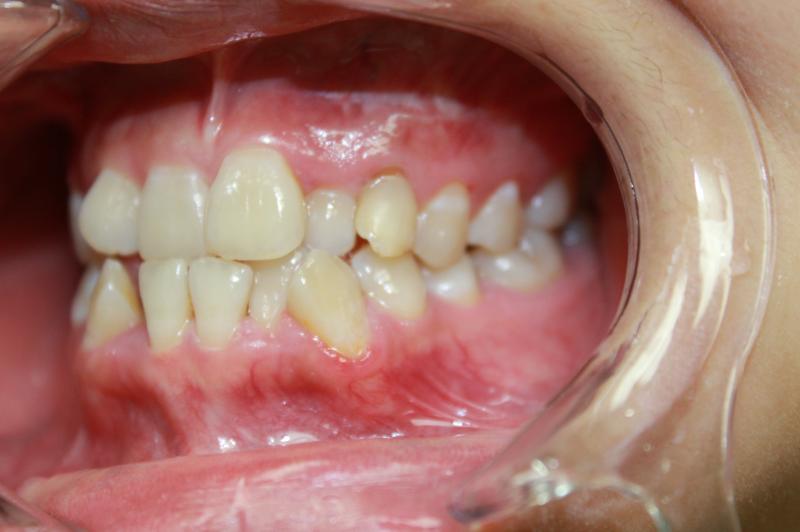

INVISALIGN - 13 months, 1 lower tooth removal, 1 series of aligners to align teeth and create the proper amount of space for 2 cantilever bridge to replace congenitally missing cuspids. COSMETIC DENTISTRY - 2 porcelain cantilever bridges and cosmetic bonding to reshape incisors and close gingival spaces. TOTAL TREATMENT TIME, 15 months

Cosmetic Dentistry, Mid-line Asymetry, Missing Teeth, Severe Crowding